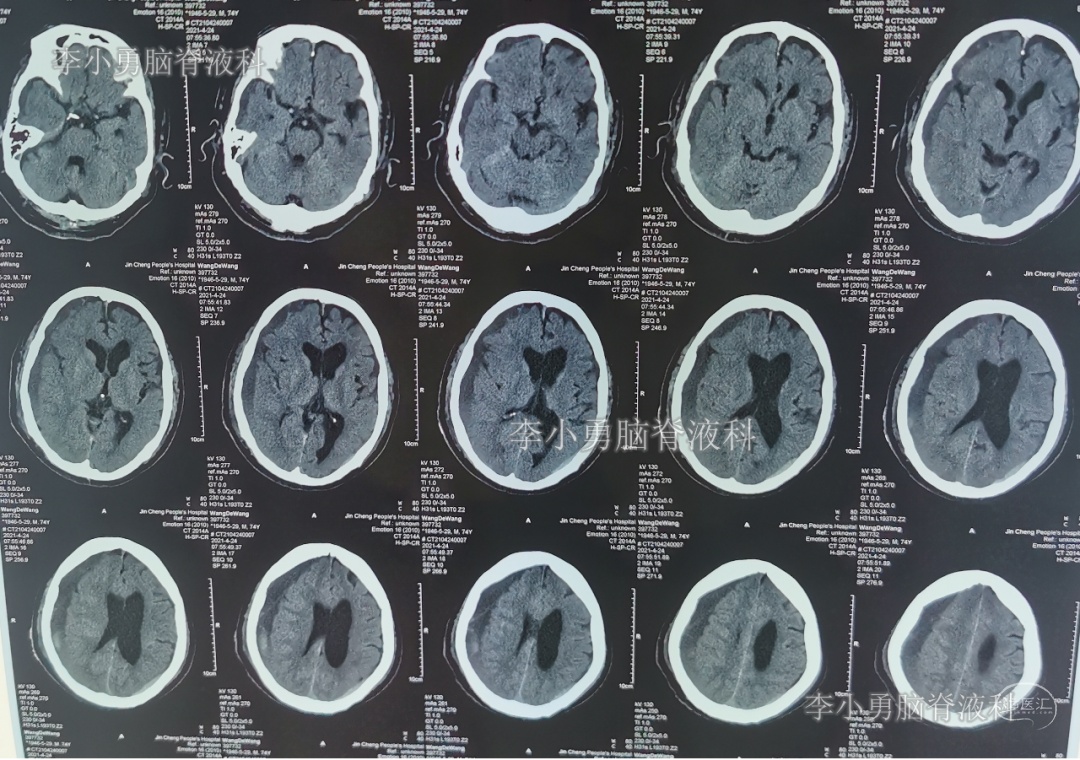

2021年4月14日(腰大池腹腔分流术后17天),头痛腿沉再次加重,复查头部CT示硬膜下血肿(图-3)。

图-3:2021年4月14日头部CT

2021年4月16日(腰大池腹腔分流术后19天),因意识变差,查头部CT(图-4)后,急诊进行了硬膜下血肿引流术,并升高分流泵的压力200。

图-4:2021年4月16日头部CT